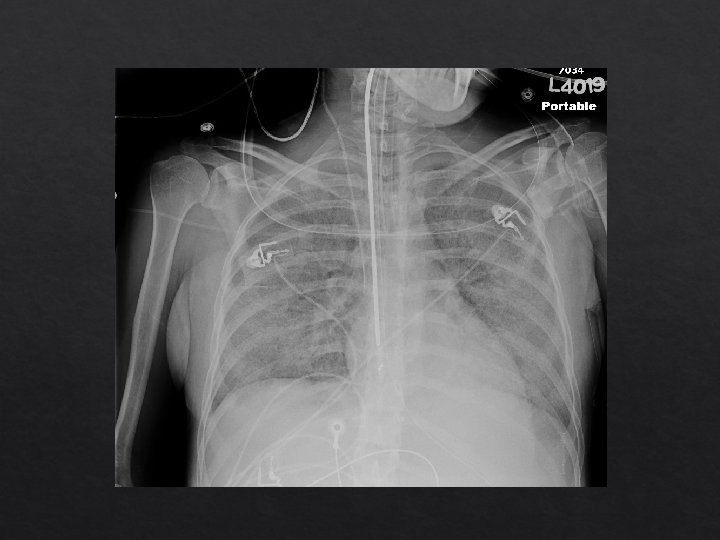

Clinical Case 35 year old lady with history of diabetes who was admitted to an outside hospital with 1 week of cough and shortness of breath. She was intubated there and transferred here for further management of her hypoxemic respiratory failure. BP: 130 s/80 s HR: 120 RR: 28 Temp: 100 Sp 02: 80% on 100% Fi 02 VC| RR 20 | Tidal volume 500 | PEEP: 15 | Fi 02: 100%

Clinical Case Gen: agitated, not following commands HEENT: no icterus Cardiac: regular rhythm, tachycardic Lungs: course breath sounds/rhonchi bilaterally Abdomen: soft/non tender Ext: warm, no LE edema

Ventilator parameters Peak pressure: 50 Inspiratory pause Plateau pressure: 35 Expiratory pause total PEEP of 20

Initial Labs 135 | 99 | 15 -------- < 160 4. 8 | 22 | 1. 0 Calcium: 9 BNP: 50 Pro 7. 7 Alb 3. 8 T-bil 0. 9 AST 34 Alk Phos 83 ALT 31 p. H: 7. 30 | PCO 2: 48 | PO 2: 50 Respiratory viral panel: pending

ARDS Definition Acute onset Bilateral infiltrates consistent with pulmonary edema Exclude cardiogenic pulmonary edema